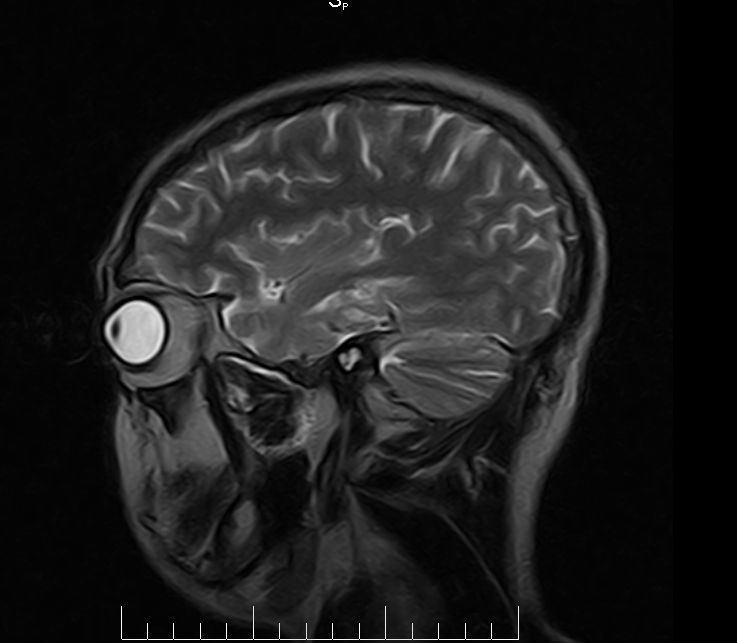

标题: MRI2379:30岁,男,癫痫10年,请各位看一下;CT示:左颞叶钙 [打印本页]

标题: MRI2379:30岁,男,癫痫10年,请各位看一下;CT示:左颞叶钙

左颞叶区见不规则点状混杂信号影

考虑血管畸形

支持2楼 左颞叶区见不规则点状混杂信号影,考虑动静脉畸形。

考虑左侧颞叶脑血管畸形(avm)。

考虑左侧颞叶脑血管畸形(avm)。----t1低等高混杂信号,t2等高信号周边较多流空血管影[冠状位明显],mra左侧大脑中动脉受压,远侧聚集.